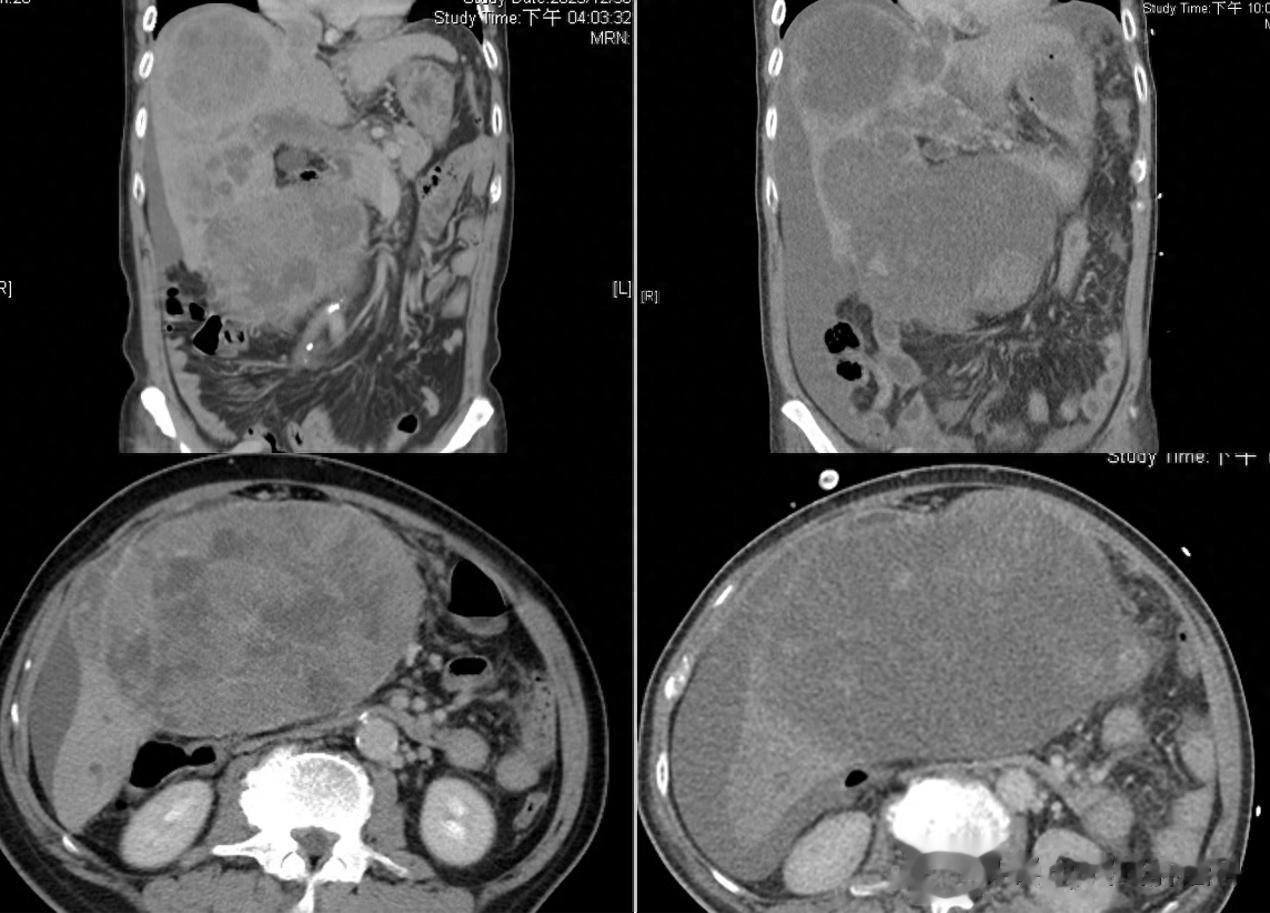

造成这位患者死亡的并非是治疗无效,反而是疗效“过好”。影像学检查中,患者原本巨大的肝脏肿块已经快速消退,呈“空心”状态。而让患者死亡的正是因为肿瘤快速消退所导致的肿瘤溶解综合征。